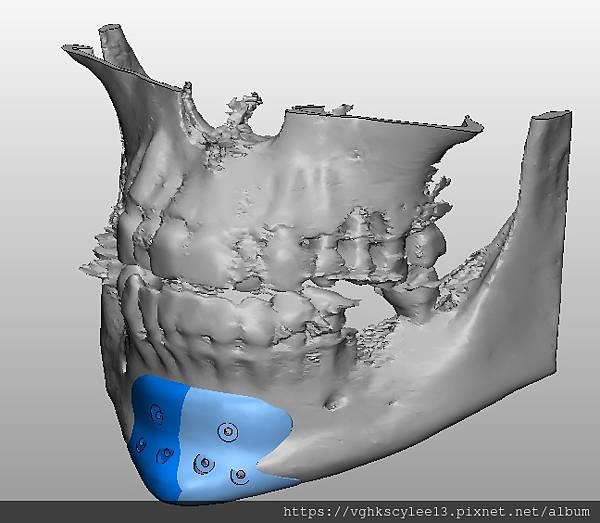

(下圖)3D模擬後工程師版的設計下巴假體的外型。

經過李醫師醫師對客戶外型的判斷,修改工程師的設計,建議更改後的假體模型(下圖)

(上圖)經過李醫師醫師對客戶外型的判斷,修改工程師的設計,建議更改後的假體模型。所以嘍,醫師的美感與專業度必須要做判斷,3D列印只是精準工具但是必須有專業醫師的判斷才可以完美!

下圖: 在李醫師確認後完美精準例印

窄小後縮的下巴,以精準3D列印技術來客製化醫師判斷後的外型下巴假體,一起改善嘴形相對的狀態。

窄小後縮的下巴,以精準3D列印技術來客製化醫師判斷後的外型下巴假體,一起改善嘴形相對的狀態。

3D模擬後 列印出吻合的設計下巴假體